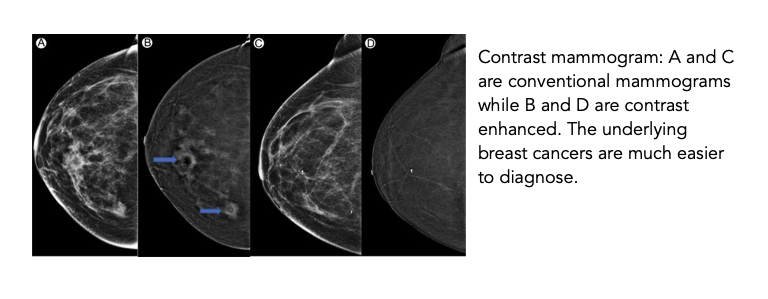

Contrast Mammography

A contrast mammogram is a conventional 3D mammogram (tomosynthesis) which is performed once intravenous contrast is given. The advantage of this technique is the contrast ‘enhances’ any cancerous lesions in the breast, making it much easier to identify. The contrast agent injected into the drip is an iodinated contrast dye (contrast that has iodine). It works by highlighting new blood vessels that form when cancers grow.